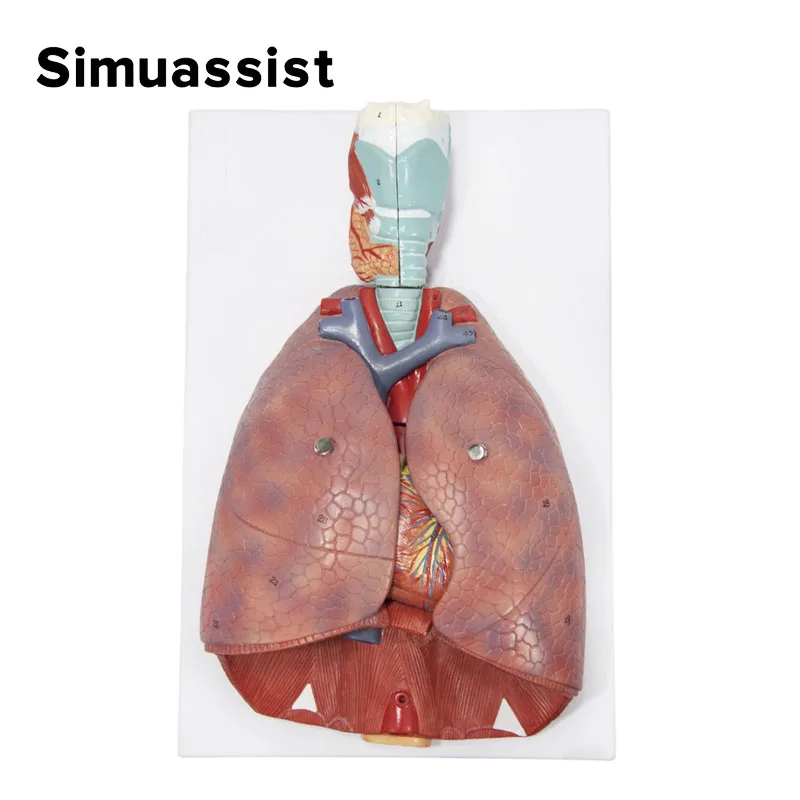

Human Larynx/Heart/Lung Anatomical Model Medical Model Pulmonary Anatomy Model Respiratory System Model Teaching Supplies

Lung Respiratory Anatomy Model Teaching System Human Display model School Lungs Anatomical Heart Educational Nasal Toy

Lung Respiratory Anatomy Model Teaching System Human Display model School Lungs Anatomical Heart Educational Nasal Toy

Lung Respiratory Anatomy Model Teaching System Human Display model School Lungs Anatomical Heart Educational Nasal Toy

Lung Respiratory Anatomy Model Teaching System Human Display model School Lungs Anatomical Heart Educational Nasal Toy